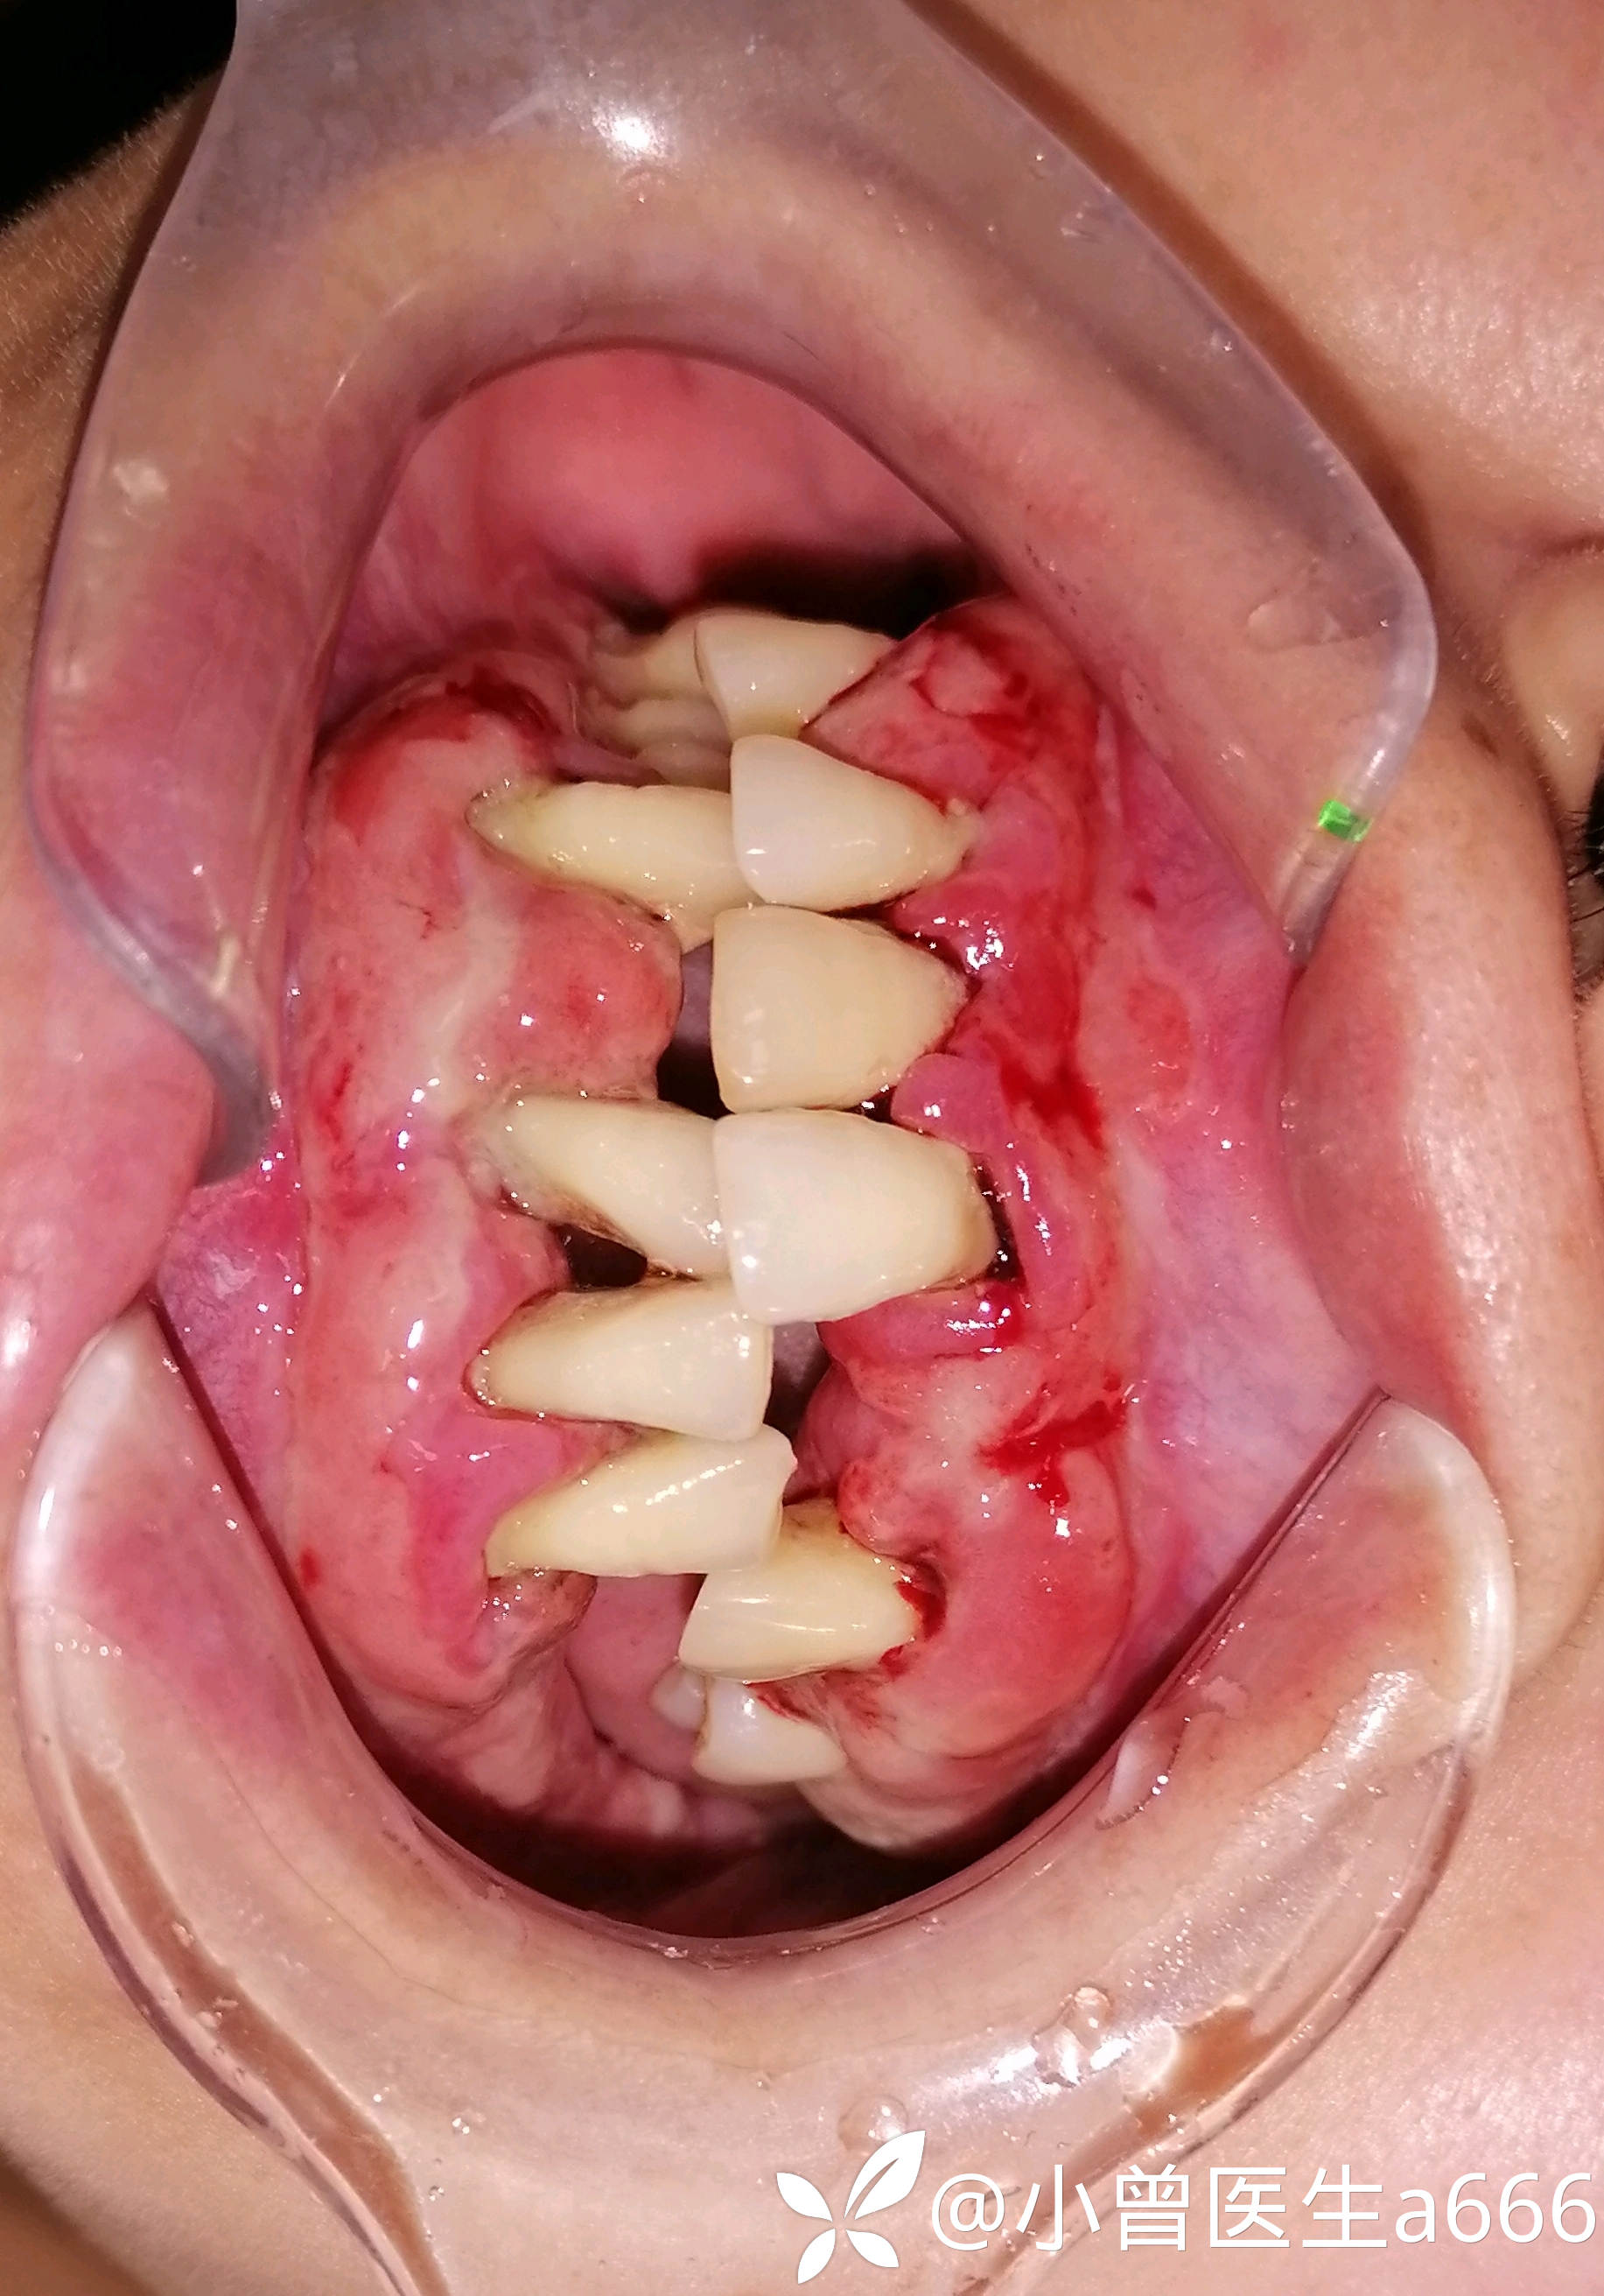

体格检查:全口牙龈红肿,探诊出血(+++),牙龈大面积溃疡溢脓,可探及深牙周袋,牙龈质软,牙龈退缩牙根暴露,见少量牙结石及软垢。牙龈牙齿检查未见疼痛不适。41缺失,41处牙龈肿胀增生至切1/3—1/2。视诊见下眼睑苍白无血色,皮肤暗黄,可见双臂皮肤斑点(患者自诉是过敏而致)

临床诊断:系统性疾病型牙周炎?